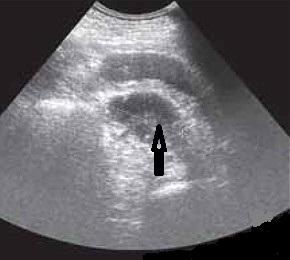

УЗИ жидкость и газ в брюшной полости

Ультразвуковая сканограмма.

Свободная жидкость (белая стрелка) и газ (чёрная стрелка) в брюшной полости.